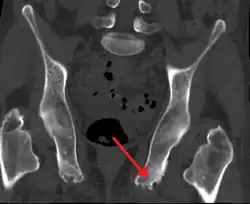

| Enthesopathy of the pelvis likely due to ankylosing spondylitis | |

An enthesopathy refers to a disorder involving the attachment of a tendon or ligament to a bone.[1] This site of attachment is known as the enthesis (pl. entheses). If the condition is known to be inflammatory, it can more precisely be called an enthesitis.

Enthesopathy can occur at the shoulder, elbow, wrist, carpus, hip, knee, ankle, tarsus, or heel bone, among other regions. Enthesopathies may take the form of spondyloarthropathies (joint diseases of the spine) such as ankylosing spondylitis, or psoriatic arthritis, plantar fasciitis, and Achilles tendinitis. Further examples include: